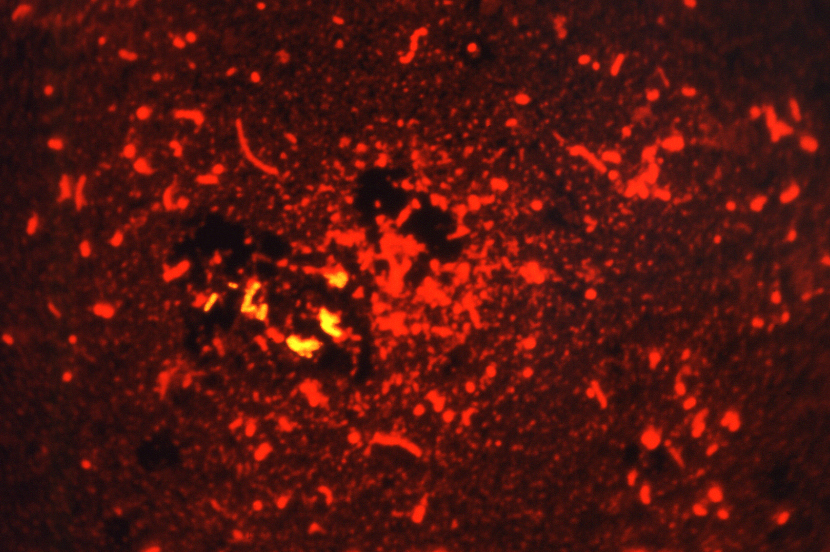

결핵의 주요 원인균은 Mycobacterium tuberculosis라는 세균입니다. 이 균은 사람 간에 전염되는 호흡기 전염균으로, 주로 감염된 사람이 기침이나 재채기, 말을 할 때 배출되는 작은 물방울을 통해 다른 사람에게 감염됩니다.

결핵균은 산소를 좋아하는 특성을 가진 균으로, 폐에 주로 감염되지만, 혈액을 통해 다른 장기에도 퍼질 수 있습니다. 결핵균은 산성 환경에서 잘 살아남고, 느리게 증식하기 때문에 진단과 치료가 늦어질 수 있습니다. 또한, 결핵균은 외부 환경에서 매우 강한 생명력을 가지고 있어, 건조하고 차가운 환경에서도 오랫동안 생존할 수 있습니다.